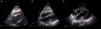

A temporary pacemaker was inserted via the right femoral vein, without immediate complications, followed by implantation of a dual chamber permanent pacemaker the next day. During this procedure, the patient presented a brief period of hypotension and pleuritic chest pain. The echocardiogram showed moderate systolic dysfunction and new moderate pericardial effusion (16 mm), with no signs of hemodynamic compromise (Figure 1). A diagnosis of iatrogenic right ventricle rupture was made and the patient was kept under clinical, electrical and echocardiographic monitoring. She presented progressive reduction of the pericardial effusion and was discharged by the 5th day, asymptomatic and without pericardial effusion (Figure 1).

Figure 1.

Echocardiographic subcostal views: (A) after permanent pacemaker implantation revealing a new moderate pericardial effusion (arrow); (B) at hospital discharge, after a few days of clinical surveillance with no evidence of pericardial effusion (arrow); and (C) at readmission, with a large pericardial effusion and ‘swinging heart’ (arrow).

Four weeks later, she was readmitted for pleuritic chest pain and asthenia. Physical examination revealed reduced heart sounds with no other significant alterations, including in the pacemaker scar, which presented no inflammatory signs. The electrocardiogram showed sinus rhythm with P-wave synchronous ventricular pacing. Blood tests showed leukocytosis (17×109/l) and elevated C-reactive protein (CRP) (110 mg/dl), with no evidence of systemic infection or fever. Blood cultures were negative and the chest X-ray showed cardiomegaly without pleural effusion. The echocardiogram revealed a large pericardial effusion (25 mm), with ‘swinging heart’ and signs of hemodynamic compromise (inferior vena cava dilatation, mitral and tricuspid flow variation >50%, abnormal septal motion, mild diastolic compression of right heart chambers), suggestive of incipient tamponade physiology (Figure 1).